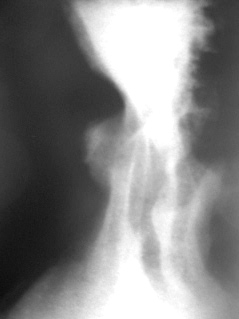

Со стороны глотки и пищевода патологических изменений не выявлено. В желудке натощак некоторое количество жидкости и слизи. В процессе заполнения желудка контрастной взвесью перистола обычная, желудок расправляется по ортотоническому типу. Складки слизистой оболочки располагаются по магистральному типу, они отечные, деформированные. В теле желудка (верхняя треть), по малой кривизне, ближе к задней стенке определяется язвенная ниша (контур-ниша) округлой формы, значительных размеров – иллюстрация 1.

1.